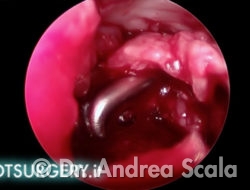

La telecamera è stata introdotta all’interno della regione calcaneale. Dal lato opposto penetra la sonda che consente di esaminare le strutture da curare. Nel caso particolare si vedono i residui della voluminosa borsite retrocalcaneale che deve essere asportata. La parte malata viene rimossa mediante strumenti motorizzati ed eliminata mediante l’aspiratore.